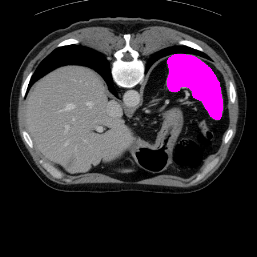

In order to assess the performance of the proposed method, we compare the performance of the proposed model with excellent models in recent years. Table 1 and Table 2 shows the comparison results of different models in setting1, while Table 3 and Table 4 shows the comparison results of different models in setting2 on the data set in recent years. PANet[25] is the most widely influential few-shot model in the field of few-shot image segmentation on natural images. SENet [18] is the first few-shot segmentation model proposed for medical images. SSL-ALPNet[19] introduced the milestone of using superpixel self-supervision to train few-shot medical image models. RPNet[29] is a supervised method with a recursive mask optimization module to iteratively optimize the segmentation mask, [27] adapt it into the same self-supervision learning framework and applies setting1 to it and denoted as SSL-RPNet; CRAPNet[27] is the latest SOTA model for 2023. Compared with CRAPNet, our method outperforms most of the state-of-the-art models and only slightly outperforms CRAPNet. Figures 3 and 4 show examples of the model’s segmentation predictions on different datasets, respectively; The first row is the support map, the second row is the label map, and the third row is the segmentation prediction of the model.